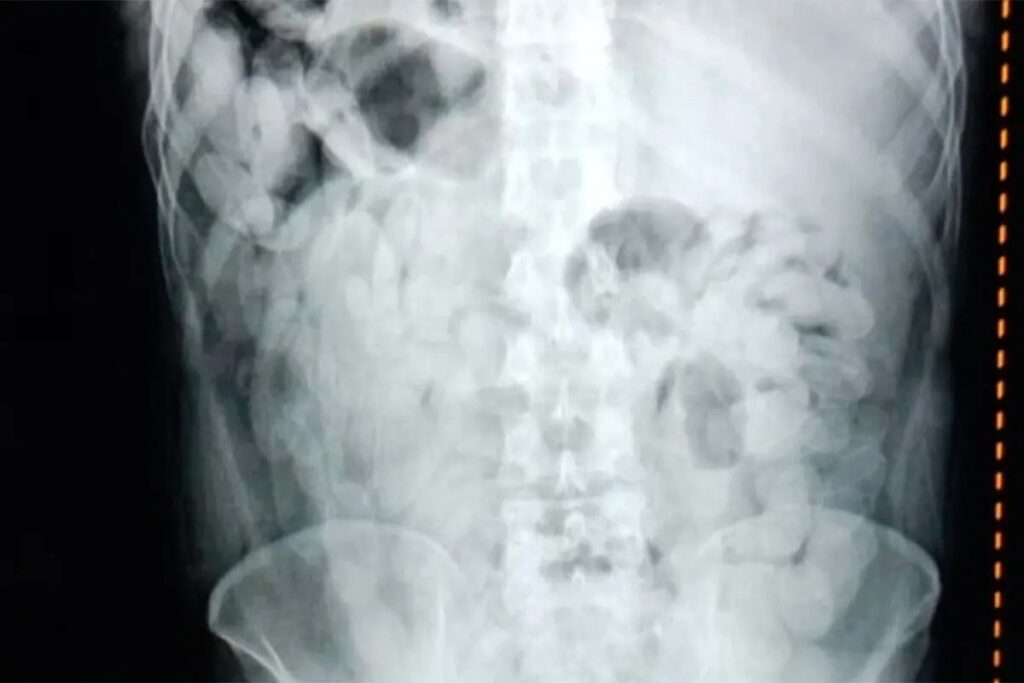

Ante la urgencia médica, los pasajeros fueron trasladados de inmediato al hospital de Trancas, donde las placas radiográficas confirmaron la presencia de múltiples cuerpos extraños en sus organismos. Bajo supervisión médica, ambos lograron evacuar 180 cápsulas que fueron sometidas a análisis de campo.

Las pruebas con reactivos narcotest confirmaron que el contenido era cocaína, con un peso total de 2 kilos 102 gramos. Según los especialistas, esta práctica es extremadamente peligrosa, ya que la ruptura de una sola cápsula puede provocar la muerte por sobredosis en cuestión de minutos.